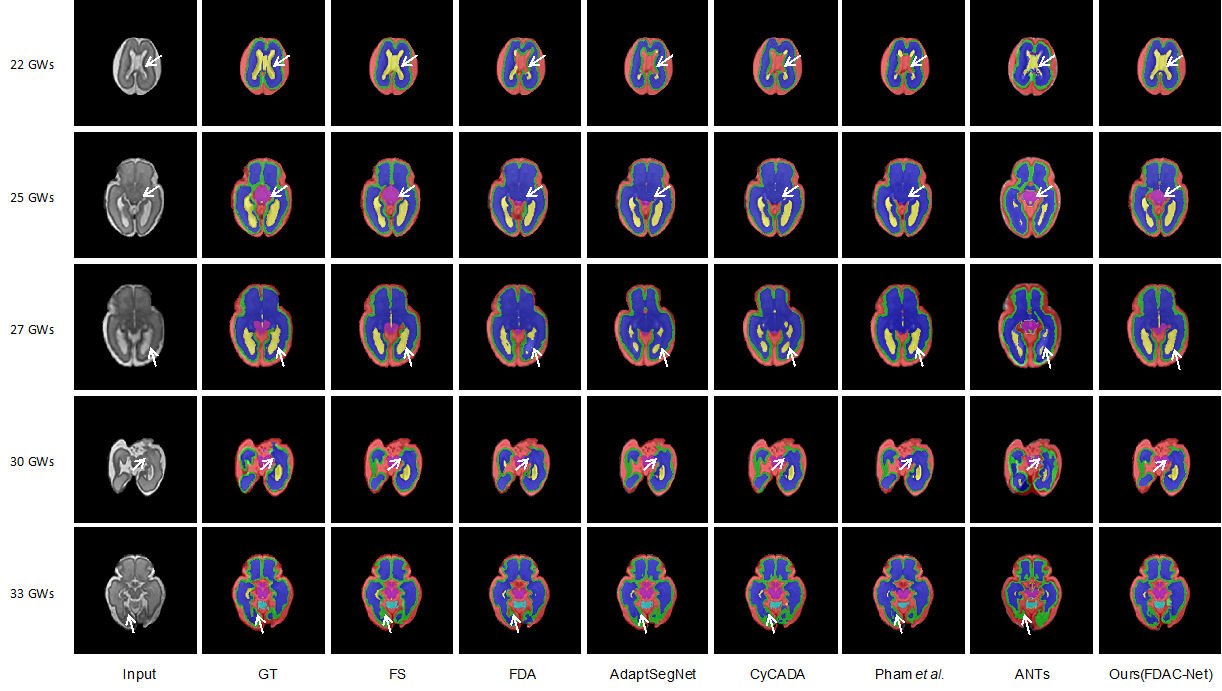

7、探索胎儿磁共振脑组织的分割方法

厚层胎儿脑磁共振(MR)扫描的准确组织分割对于重建各向同性脑MR体积和量化胎儿脑发育至关重要。然而,由于胎动不可避免,在临床获取的胎儿磁共振脑影像往往采用快速采集序列,导致采集得到的胎儿脑磁共振影像是厚层的。由于厚层扫描图像质量较低,组织对比度差,且存在运动和伪影,因此直接对厚层扫描图像进行分割面临着巨大挑战。为此,研究人员提出了一种方法,利用高质量各向同性胎儿脑MR图像(及其相应的注释)作为厚层扫描图像分割的指导。鉴于高质量各向同性图像(即源数据)和厚层扫描图像(即目标数据)之间存在显著的差别,研究人员采用领域自适应技术来实现知识的有效转移(从高质量“源”图像到厚层“目标”图像)。并提出了一种新颖的循环一致域自适应网络(C2DA-Net),以有效地传递从高质量各向同性图像中学到的知识,实现对厚层扫描图像脑组织的准确分割。在372个临床获取的厚层MR扫描图像的大规模数据集上进行的大量实验表明,C2DA-Net在定量和定性方面均优于其他方法,表现出更好的性能。成果的代码已在https://github.com/sj-huang/C2DA-Net 上公开提供。

图2 提出的模型与现有代表性方法的效果对比。

相关研究成果以“Tissue Segmentation of Thick-Slice Fetal Brain MR Scans with Guidance from High-Quality Isotropic Volumes”为题发表于IEEE Transactions on Biomedical Engineering。九游体育(www.jiuyou.com)官方网站沈定刚课题组博士研究生黄世杰为第一作者,九游体育(www.jiuyou.com)官方网站常任正教授沈定刚为通讯作者,九游体育(www.jiuyou.com)官方网站为第一完成单位、上海临床研究中心为合作单位。